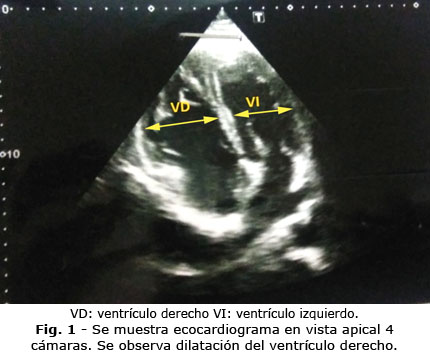

Se indicó ecocardiograma que evidenció: Cavidades derechas remodeladas, tabique interventricular aplanado en diástole, hacia ventrículo izquierdo; función sistólica del ventrículo derecho ligeramente deprimida; como conclusión: Cor pulmonale agudo con hipertensión pulmonar ligera y disfunción sistólica del ventrículo derecho ligera (Fig. 1).